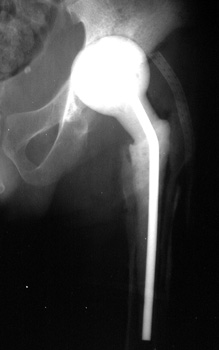

INFECTION—Markedly widened interfaces about acetabular and femoral components

INFECTION Progressive interface widening about acetabular component